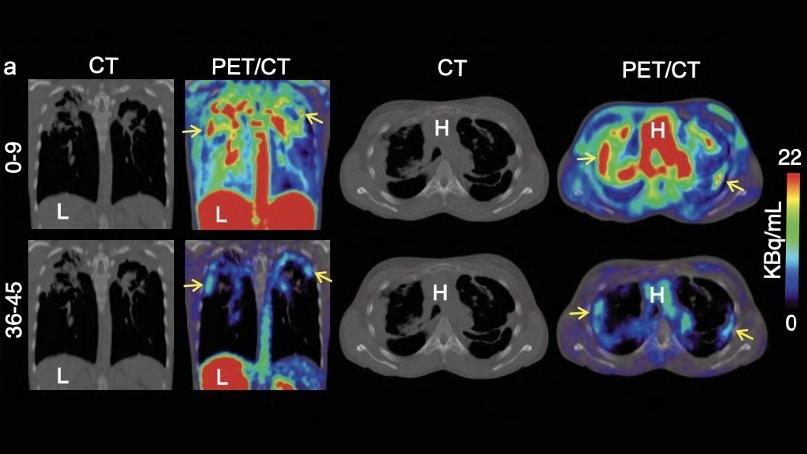

PET Imaging Method Detects Inflammation in Body

Researchers at Dana-Farber Cancer Institute (Boston, MA, USA; www. dana-farber.org) have developed the first ever probe capable of identifying general inflammation with high sensitivity through whole-body imaging. This breakthrough technique, which uses positron emission tomography (PET) imaging to detect inflammation, could be used in clinical settings to guide treatment choices for inflammation-related conditions, monitor responses to anti-inflammatory drugs and cancer immunotherapies, and assist in diagnosing diseases linked to chronic inflammation.

Image: The diagnostic tool could improve diagnosis and treatment decisions for patients with chronic lung infections (Photo courtesy of SNMMI)